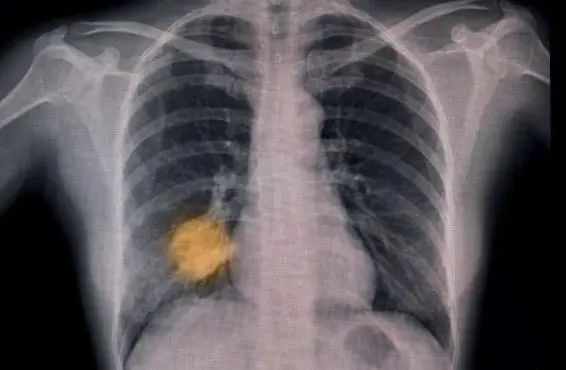

另一項(xiàng)進(jìn)行中的試驗(yàn)正在追蹤英國(guó)6家醫(yī)院的15萬(wàn)名患者,測(cè)試AI能否根據(jù)胸部X光片作出肺癌早期診斷,發(fā)現(xiàn)哪些患者需要當(dāng)天接受計(jì)算機(jī)斷層掃描(CT)。

人工智能工具的試驗(yàn)和兩年一次的篩查有望幫助人們更早地發(fā)現(xiàn)肺癌。

圖片來(lái)源:《自然·醫(yī)學(xué)》